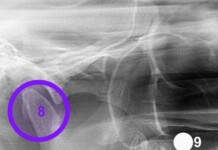

O médico Pedro Gomes detalha como funcionam os métodos. O DIU Mirena é colocado dentro do útero e libera hormônio continuamente, podendo durar até 8 anos. Já o Implanon é um pequeno bastão inserido sob a pele do braço, com ação por até 3 anos. Ambos evitam a gravidez, mas não protegem contra infecções sexualmente transmissíveis, por isso a recomendação é manter o uso de preservativos.